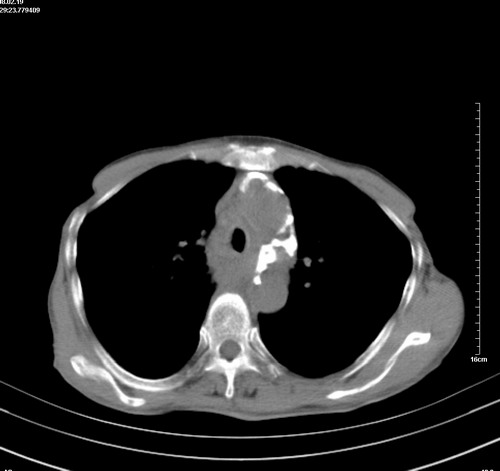

病人,女,79岁,主要因腹疼二月入院,彩超,肝,胆,脾,未见异常,胸透上消化道造影未见异常,化验白细胞增高,内科医生让做胸部ct检查,因为熟人多做了腹部(外科会诊考虑胆囊炎).现ct片如下请假各位战友.

中后纵隔占位,气管、食道受压、变形、移位。恶性可能性大。

考虑:中后纵隔转移瘤可能性大,主动脉硬化。

1 气管旁、隆突下淋巴结明显肿大,肝左叶外侧段低密影,都考虑转移。

纵隔淋巴结肿大,考虑转移而来

肺癌,纵隔淋巴结转移,肝左叶病变考虑为转移病灶。

后中纵隔团块影,伴气管、食道受压移位,首先考虑转移瘤,肝s5段低密度灶。建议增强检查,另外其结肠是否有问题请提供,右肺部分肺叶局限含气增多,考虑局限肺气肿。

建议强化检查,考虑纵隔型肺癌,小细胞可能性大。

后中纵隔团块影,伴气管、食道受压移位,首先考虑转移瘤,肝表现同11773。

后中纵隔淋巴结肿大,首先考虑转移瘤。